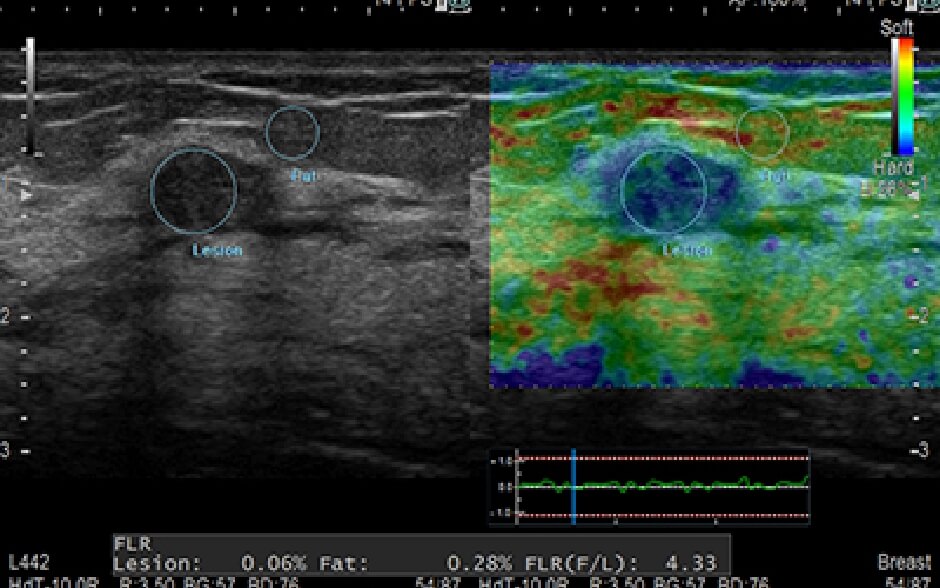

ABUS

乳房用超音波画像診断装置

超音波検査の最大のハードルは,組織を的確かつ鮮明に描き出すためには高度な検査者スキルを要するということでした。当院のABUSは、簡単な操作で検査者のスキルに左右されることのない乳腺エコーを可能としています。